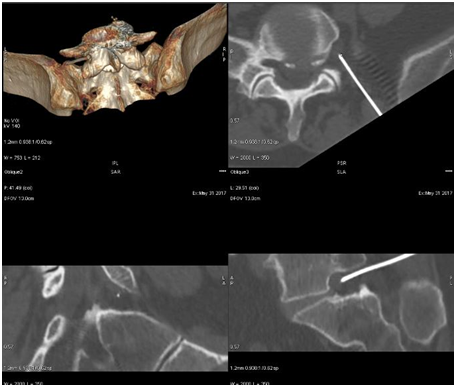

The technique of ozone discolysis under the control of CT with navigation

The patient placed on the abdomen, the roller under the belly at the place of planned injection should slightly widen the intervertebral space. The first scan (so-called Scout view) ensures the planning of the procedure. After the chosen area scan is performed, the needle path is planned in the target of intervertebral space. Subsequently, a 0.7/120 mm puncture needle (22G Braun) is punctured under the surface anesthesia at the exact location of the laser point - ideally in the patient's exhalation phase. After contact with the resistance of the annulus fibrosus, a control scan and 3D reconstruction are performed to determine the accuracy of the puncture. If the correct location of the needle and its path is confirmed, the steroid (diprophos) and the local anesthetic (bupivacaine) are administered. After a while, the needle is inserted into the central part of the disc and a syringe containing 20 ml of the ozone mixture at a concentration of 30 micrograms per liter is connected to the needle. Gas is slowly injected until sense of resistance of the piston (typically 3-5ml), the remaining volume of gas is left on the side wall of the disc and the vertebral body as an additional anti-inflammatory and oxygenating effect of the tissue. After placing the dressing, the patient in the lying position is taken to the observation room, where he spends 2-6 hours depending on the need. The patient is discharged with the recommendation to rest 48 hours and avoid prolonged sitting for the next 2 weeks after the procedure (Figure 2).

Figure 2 Ozone discolysis level L4 / L5.